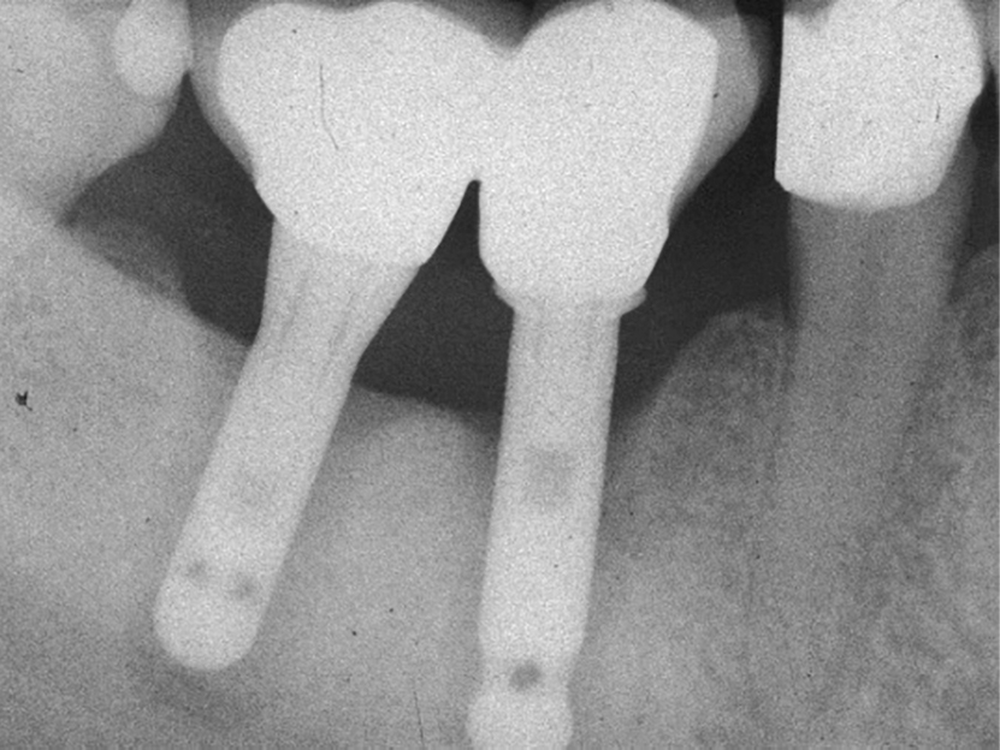

– la péri-implantite définie comme une inflammation des tissus mous péri-implantaires avec une destruction irréversible de l’os péri-implantaire (fig. 2a-b).